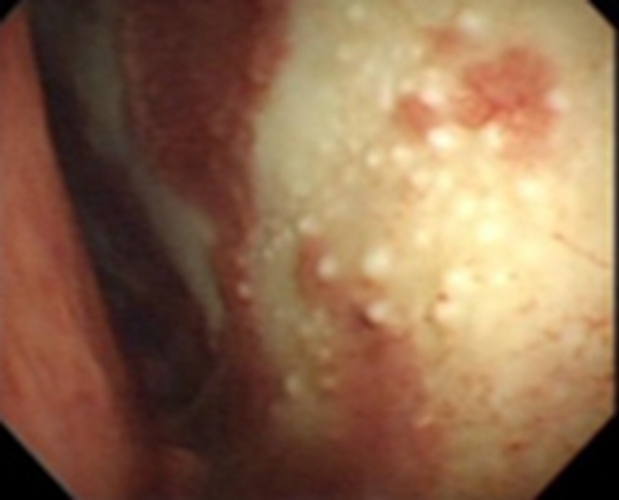

結核性胸膜炎胸腔鏡

結核性胸膜炎胸腔鏡的